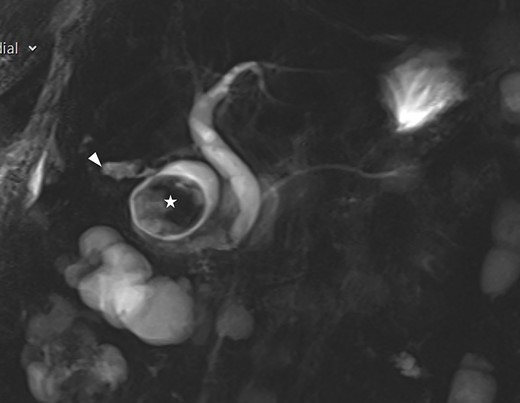

A frail 83-year-old female attended the emergency department with epigastric pain, vomiting and signs of sepsis with a heart rate of 101 and a temperature of 38°C. She had a recent admission with severe cholecystitis that was managed conservatively with intravenous antibiotics. On examination, she had tenderness in the right upper quadrant. Blood revealed an acute kidney injury, a CRP of 189 with normal liver function tests. Axial imaging demonstrated aerobilia with a dilated common bile duct of 14 mm and there was a 3.5 cm stone impacted in the first part of duodenum with evidence of a cholecysto-duodenal fistula (Figs 1–3).

CT scan showing the stone impacted in the first part of duodenum.

MRI scan showing the gallbladder adherent to the duodenum with an impacted stone in the duodenum.